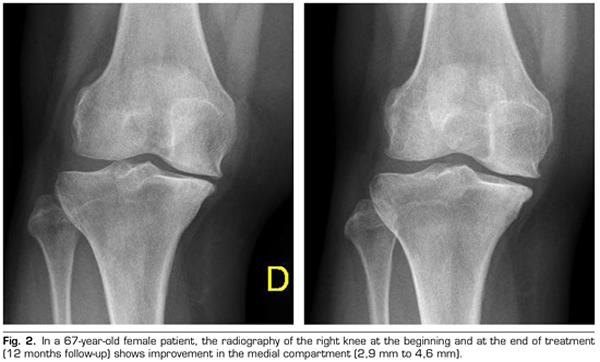

Radiological variables: In 53 patients analyzed radiologically (according to standardized protocol) at one year of follow-up after ozone treatment, the internal compartment increased significantly from 4.12 ± 1.41 mm to 4.4 ± 1.35 mm (p = 0.0008) and the external compartment increased from 6 ± 1.37 to 6.16 ± 1.4 mm (p = 0.0753).

Figure 2